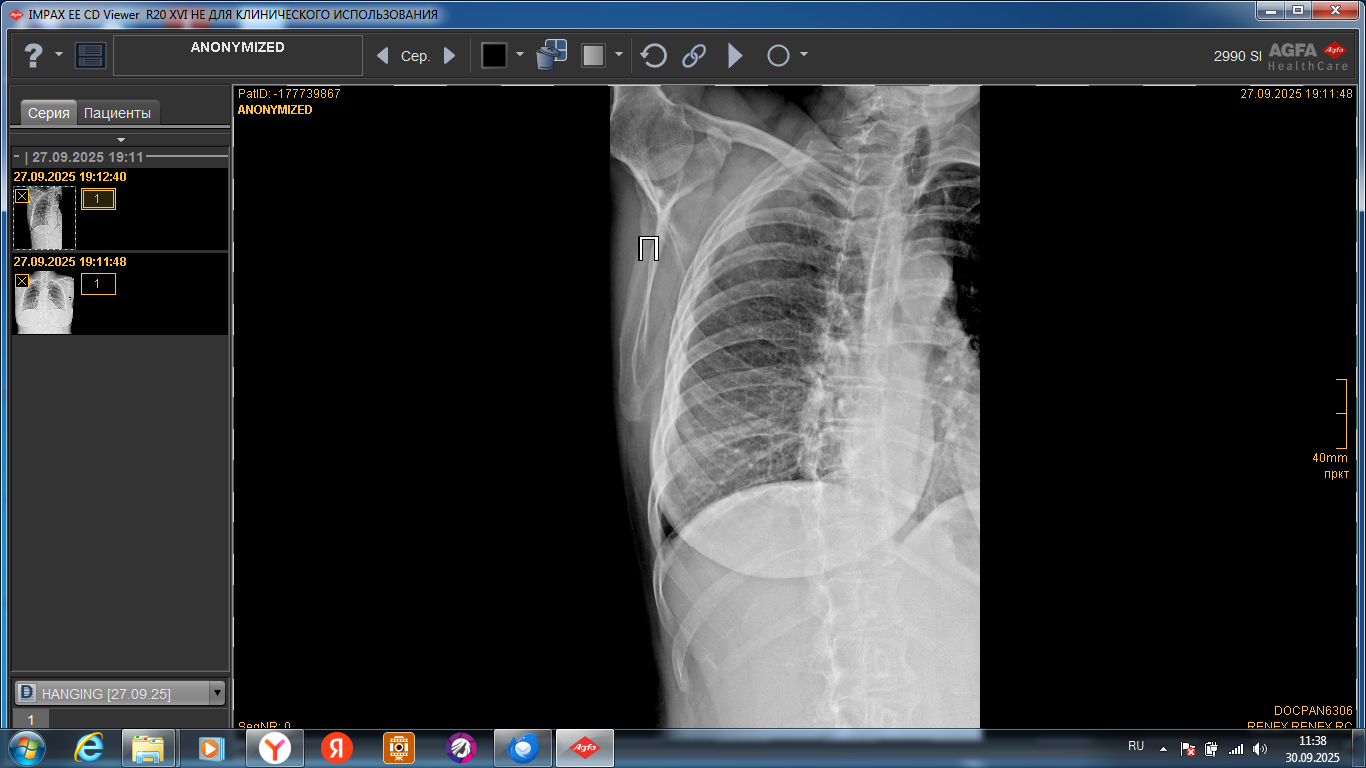

После падения, в гололед, перелом среднего пальца, на левой руке. Гипс …